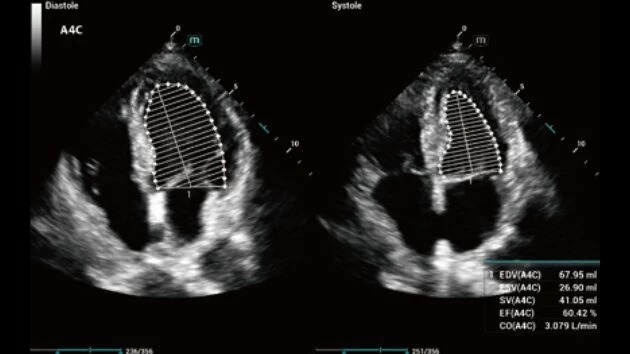

Ультразвуковой аппарат Mindray Consona N7 принадлежит к категории устройств экспертного класса и предназначен для проведения широкого спектра общей диагностики. Благодаря высокому уровню визуализации, он активно применяется в кардиологии, а также для гинекологических исследований.

Тканевой допплер:

Да

• Echo Boost для улучшенной визуализации структур сердца